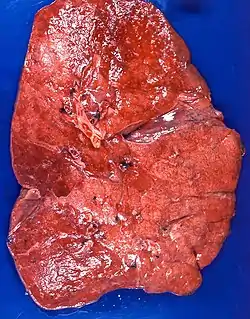

Appearance

The gross appearance of a lipid pneumonia is that in which there is an ill-defined, pale yellow area on the lung. This yellow appearance explains the colloquial term "golden" pneumonia.[7]